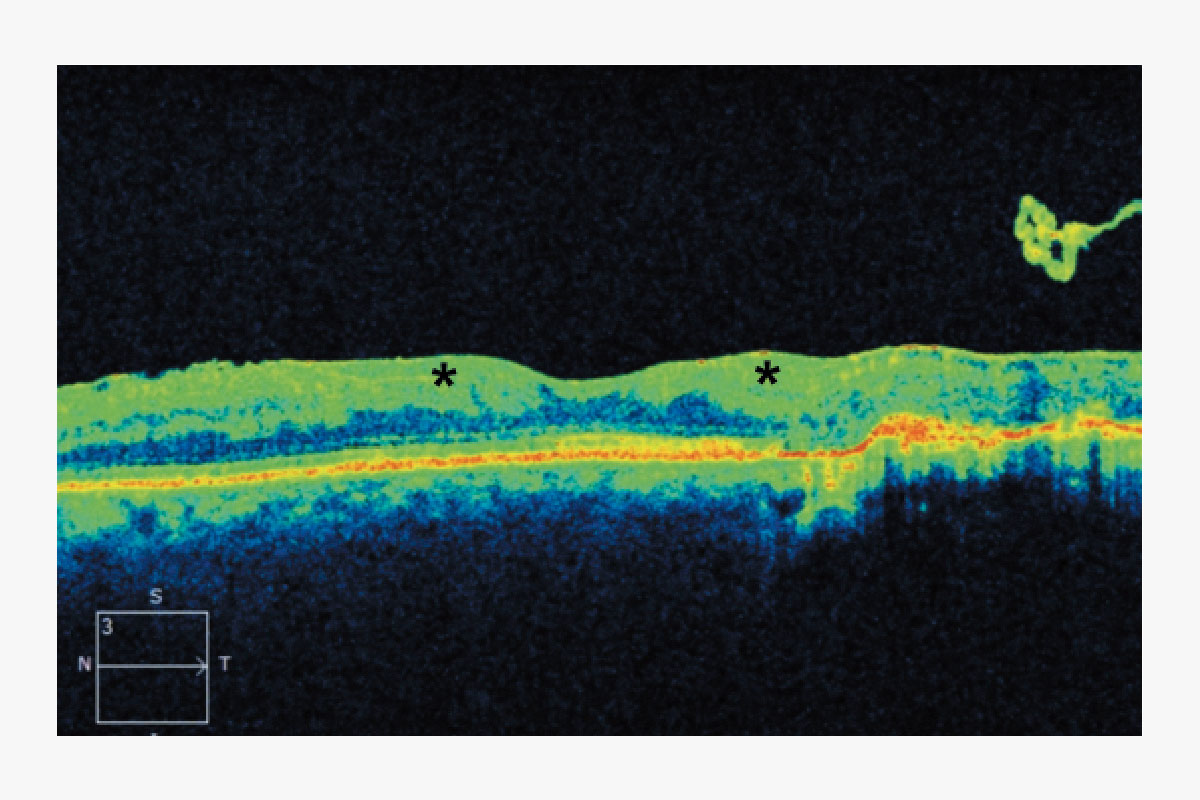

Figura 1. Tomografía de coherencia óptica de un varón de 41 años con antecedentes de retinopatía diabética proliferativa que muestra una desorganización de las capas internas de la retina (asteriscos).

Los cambios patológicos más específicos, como la desorganización de las capas internas de la retina (DRIL; Figura 1), solo pueden apreciarse mediante OCT y se han identificado como marcadores del potencial visual y predictores de la progresión de la RD.4 Del mismo modo, la alteración de la retina externa (Figura 2) y el daño temprano de los fotorreceptores pueden indicar una enfermedad más avanzada con un pronóstico visual desfavorable.5